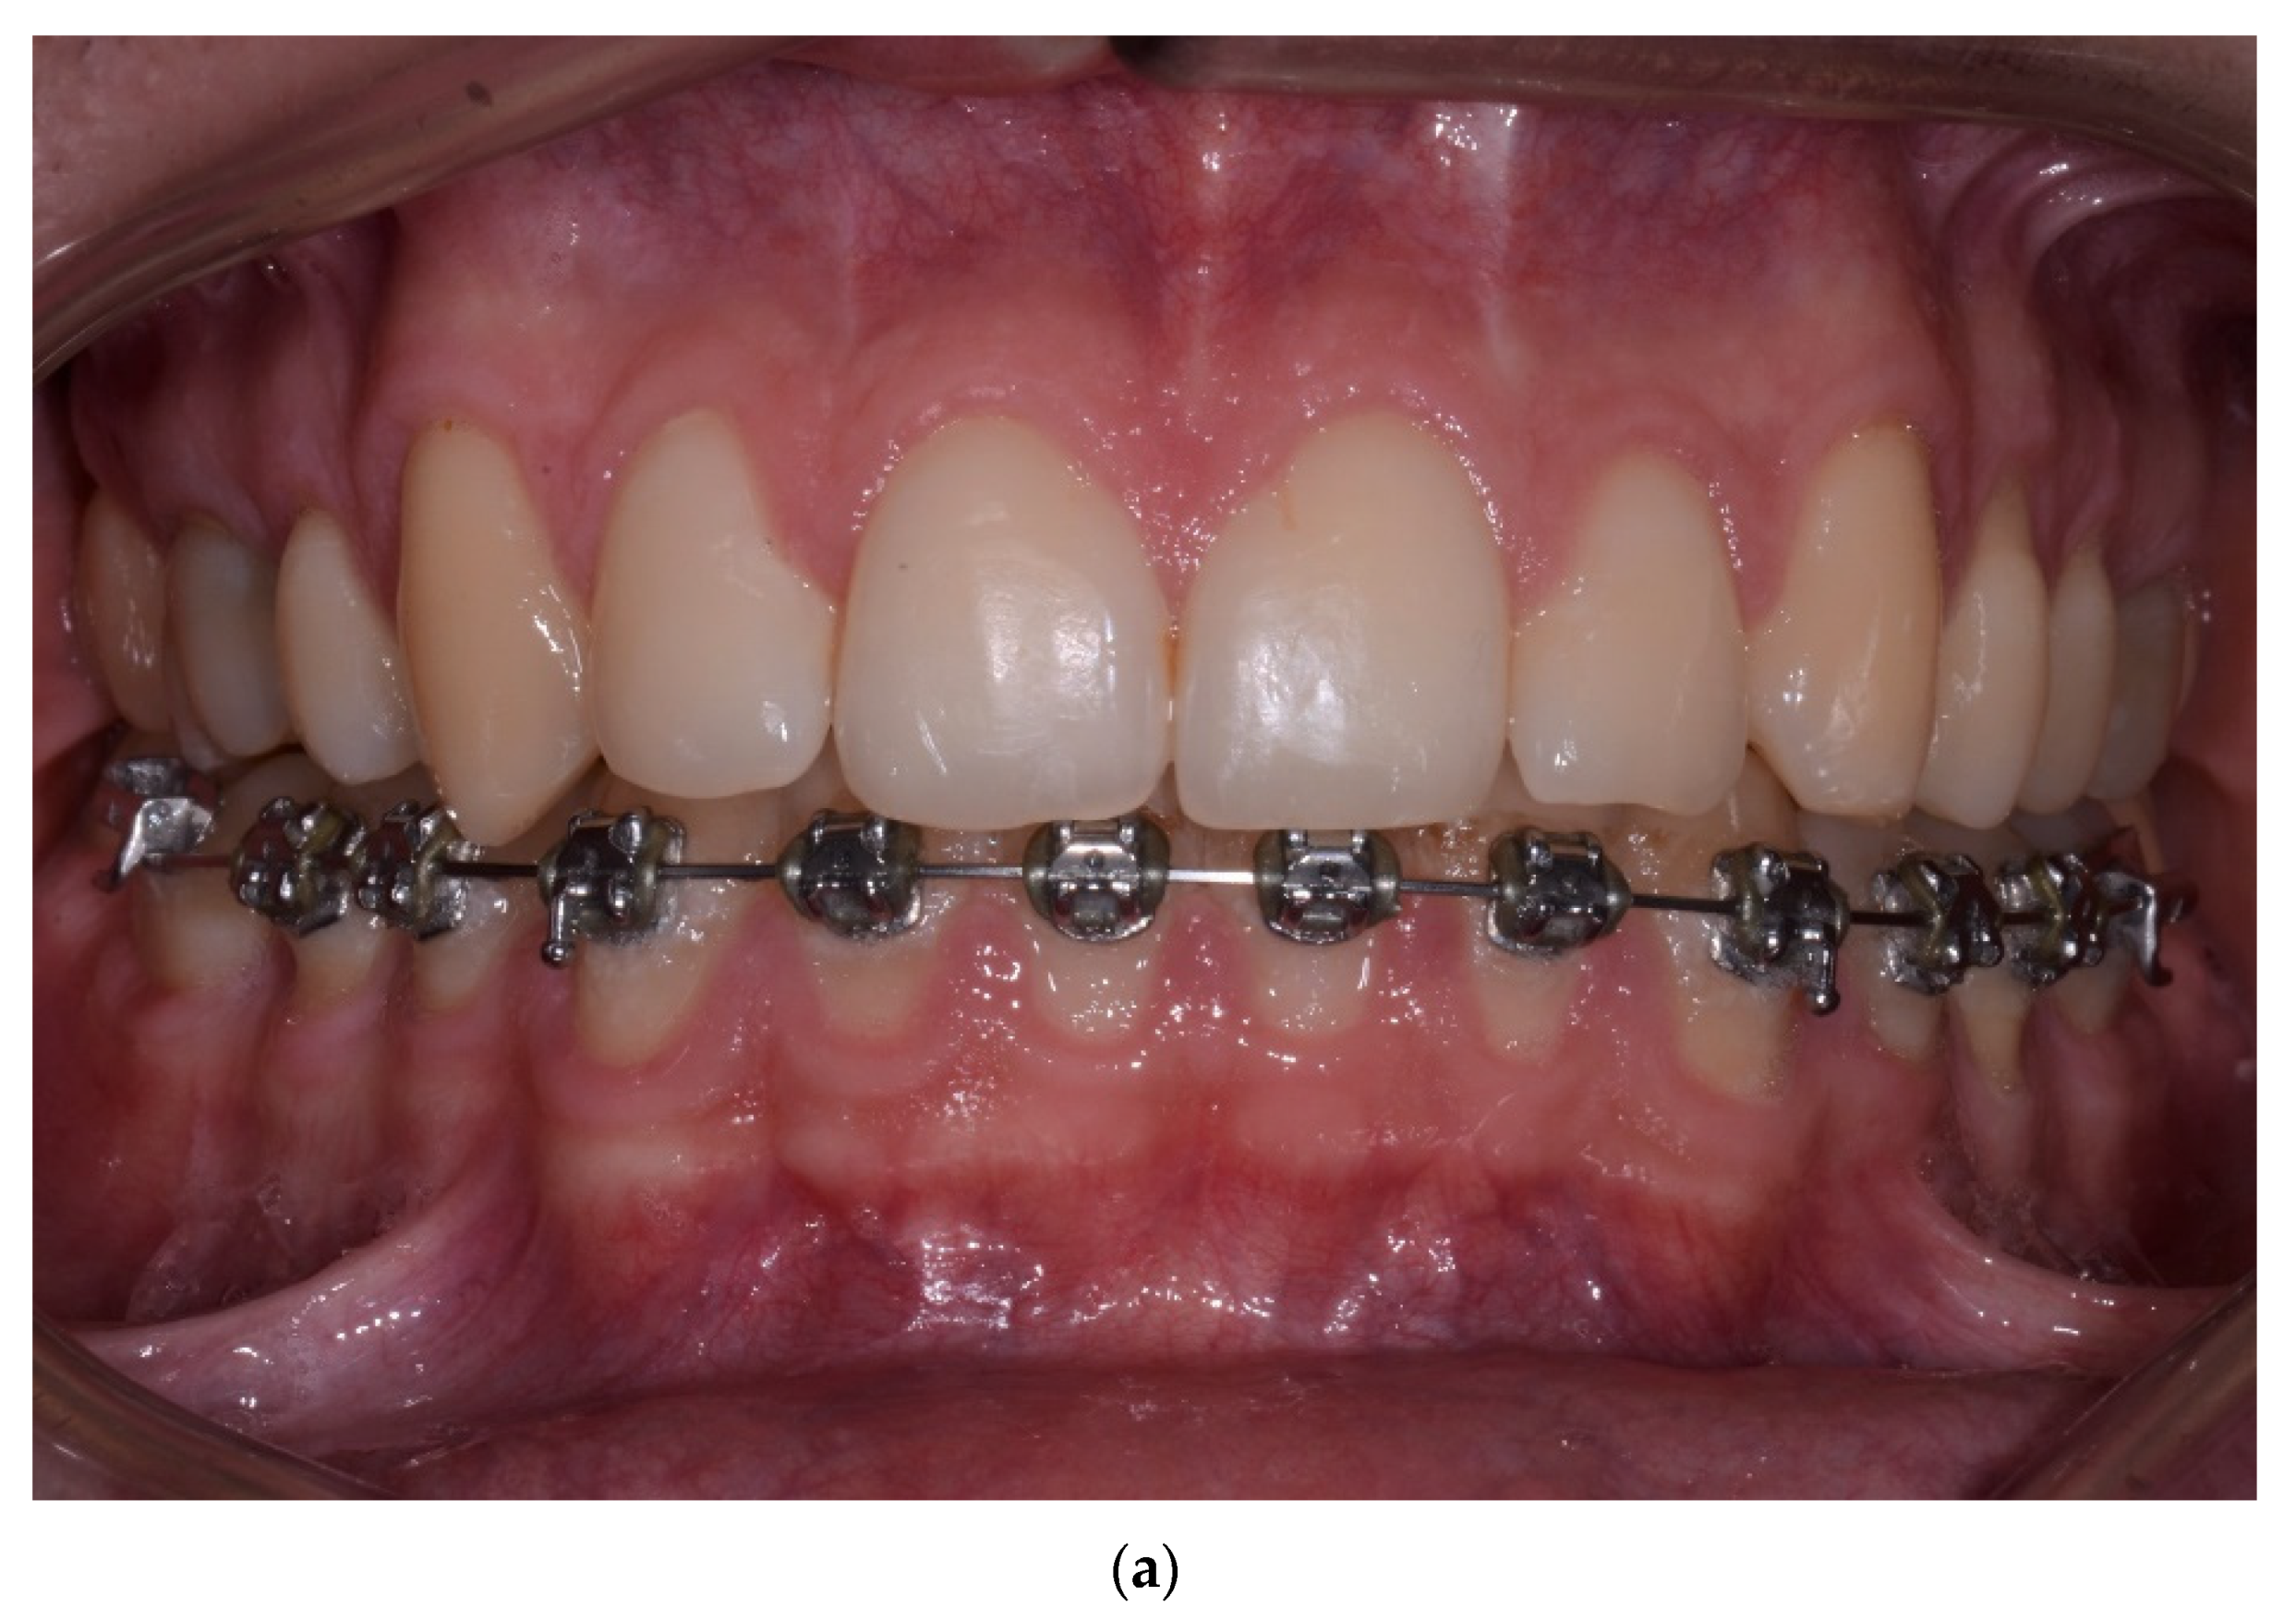

| Parameter | [%] | Time of Observation | Difference between 1 Year and a Minimum of 5 Years Post-op | p-Value | Mean Diff. (95% Cl) between 1 Year and a Minimum of 5 Years Post-op |

|---|---|---|---|---|---|

| FMPI | x ± SD | Baseline 17.33 ± 2.11 1 year 16.90 ± 2.25 5 years 17.20 ± 2.18 | +0.30% | p = 0.699 * | 0.42 (−0.91, 1.75) |

| FMBOP | x ± SD | Baseline 13.44 ± 1.87 1 year 13.24 ± 1.75 5 years 13.32 ± 1.46 | +0.08% | p = 0.724 ** | 0.26 (−0.61, 1.12) |

| Parameter | [mm] | Time of Observation | Difference between 1 Year and a Minimum of 5 Years Post-op | p-Value | Mean Diff. (95% Cl) between 1 Year and a Minimum of 5 Years Post-op |

| PD | x ± SD | Baseline 2.74 ± 0.57 1 year 2.48 ± 0.51 5 years 2.28 ± 0.48 | −0.20 mm | p < 0.0001 * | −0.23 (−0.29, −0.16) |

| CAL | x ± SD | Baseline 2.75 ± 0.57 1 year 2.49 ± 0.51 5 years 2.48 ± 0.86 | −0.01 mm | p = 0.0350 * | −0.04 (−0.17, 0.10) |

| BS | x ± SD | Baseline 4.76 ± 0.94 1 year 4.49 ± 0.77 5 years 4.29 ± 0.70 | −0.20 mm | p = 0.2430 * | −1.11 (−1.43, −0.79) |

| Parameter | [mm] | Time of Observation | Difference between 1 Year and a Minimum of 5 Years Post-op | p-Value | Mean Diff. (95% Cl) between 1 Year and 5 Years Post-op |

| Phenotype | x ± SD | Baseline 1.71 ± 0.52 1 year 2.03 ± 0.47 5 years 1.99 ± 0.50 | −0.04 mm | p = 1 * | −0.02 (−0.05, 0.02) |

| PW | x ± SD | Baseline 3.75 ± 0.92 1 year 3.54 ± 1.50 5 years 4.03 ± 0.89 | +0.49 mm | p = 0.103 * | 0.38 (0.18, 0.58) |

| PH | x ± SD | Baseline 4.82 ± 1.16 1 year 4.00 ± 1.60 5 years 4.29 ± 3.56 | +0.29 mm | p = 0.057 * | 0.19 (−0.40, 0.78) |

| GR | x ± SD | Baseline 0.13 ± 0.47 1 year 0.07± 0.32 5 years 0.19 ± 0.79 | +0.12 mm | p = 1 * | 0.11 (0.01, 0.21) |

| RW | x ± SD | Baseline 0.21 ± 0.75 1 year 0.10 ± 0.49 5 years 0.14 ± 0.59 | +0.04 mm | p = 1 * | 0.02 (−0.07, 0.12) |

| KT | x ± SD | Baseline 5.02 ± 1.79 1year 5.12 ± 1.78 5 years 5.12 ± 1.72 | 0.00 mm | p = 1 * | −0.03 (−0.23, 0.18) |